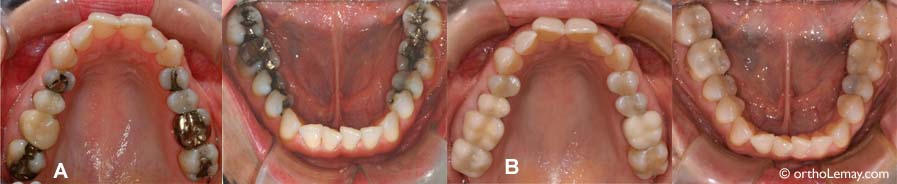

Matériaux restauratifs; amalgame, composite, porcelaine, etc.

(A) Plusieurs restaurations en amalgame sont présentes sur les dents postérieures des deux arcades. (B) Apparence plus esthétique des nouveaux matériaux (composite et porcelaine) ayant remplacé les “vielles” obturations et une couronne. A noter qu’il s’est écoulé 8 ans entre les séries de photos, période pendant laquelle la patiente ne pouvait envisager l’orthodontie mais en avait profité pour faire remplacer ses restaurations. La majorité de ces restaurations auraient pu être faites après les corrections orthodontiques.